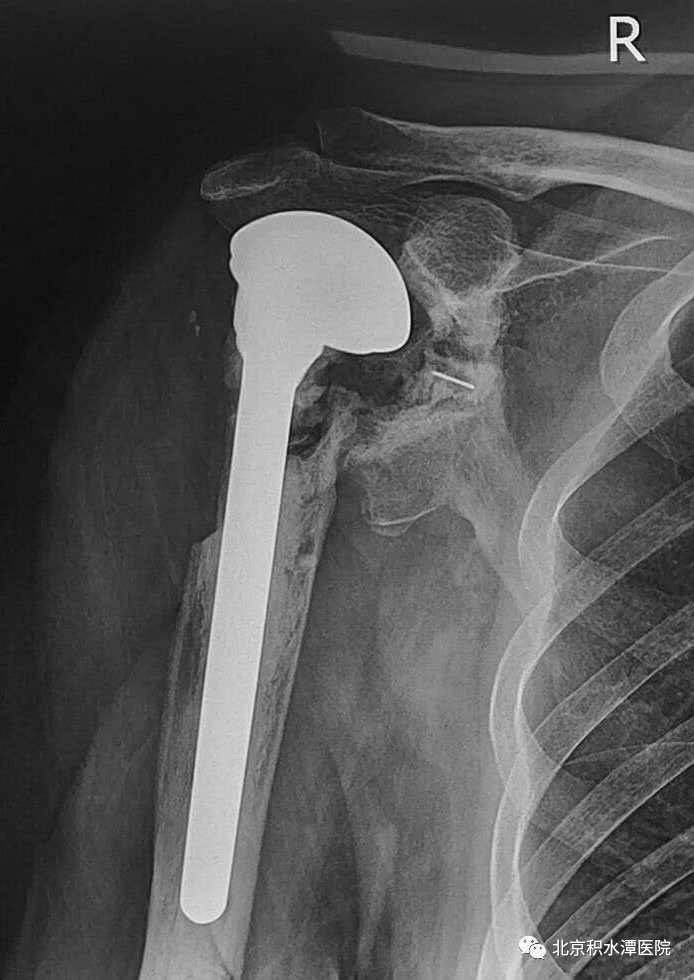

定期复查炎症指标,感染控制良好,但患者功能差,虽然带spacer无疼痛,但越来越觉得肩关节不舒服,同时想改善功能。2021年5月,患者再次回到北京积水潭医院,寻求反肩治疗改善功能。但此时患者肱骨近端大节段骨缺损、大小结节移位、肩袖组织挛缩、肩盂骨缺损严重,这种骨性状态对于反肩治疗难度很大,肩盂侧假体也无法安放与把持、现有肱骨侧假体长度不足、近端无骨性结构保护。蒋协远教授与黄强主任医师、查晔军副主任医师等讨论后,决定先为患者实行肩胛盂重建手术,并设计定制相关假体,为后期置换做准备。

术后患者复查CT,见肩胛盂骨性重建良好。但为解决现有假体长度不足的问题,此次术后,蒋协远教授、黄强主任医师就带领团队医生与工程师团队进行了反复沟通,开始设计并定制合适的反肩假体。按健侧长度计算,肱骨近端骨缺损约8厘米,起初还在肿瘤型假体和APC方式间反复讨论,最后决定采用定制反肩假体结合异体骨(APC)的方式进行处理,同时还定制了相应长度的异体骨,以更好地恢复上肢长度和三角肌张力。